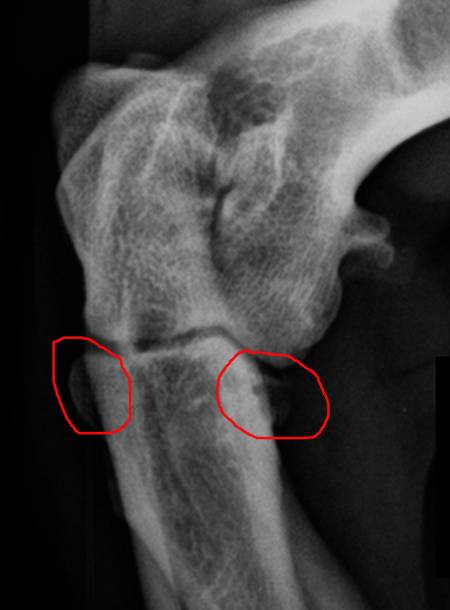

Ich habe einfach Angst, dass diese Entzündung, die der Arzt auf dem Bild erkennen konnte (rot eingekreist) mehr wird.

Daher trag ich ihn jetzt die Treppe runter.

Hier sieht man nochmal die Stelle, die Entzündet ist:

Links schlimmer als rechts.Was sagt ihr dazu?